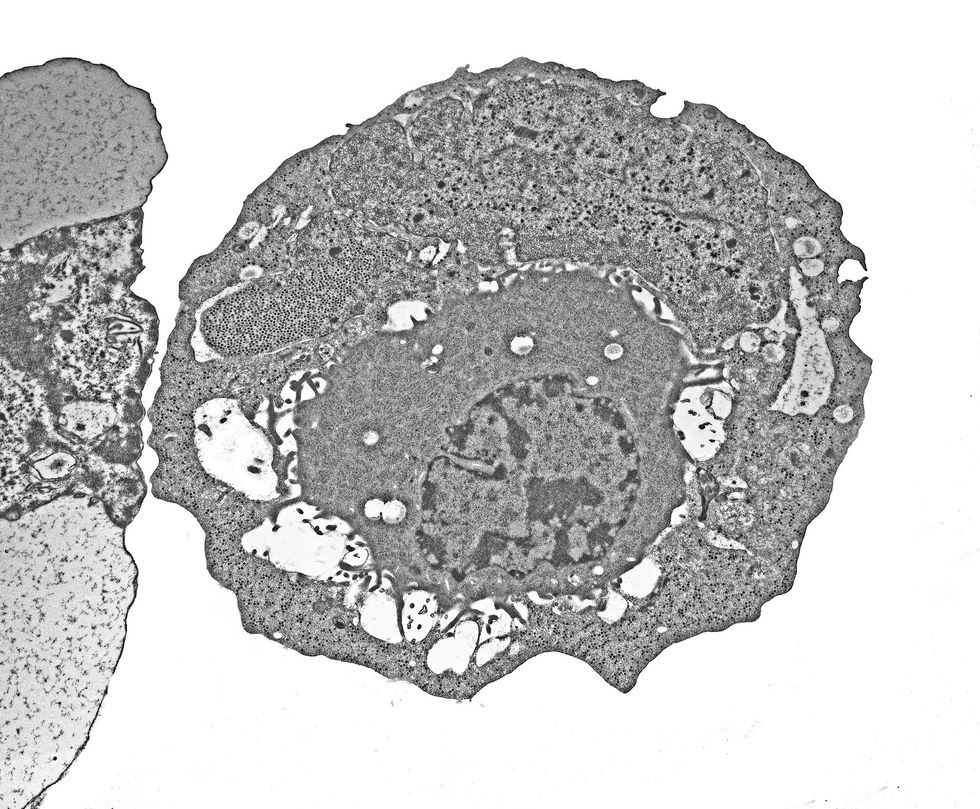

Experts say what we're dealing with is adenovirus, a group of respiratory viruses that have been around for ages.

"What we're seeing in the news, often called a 'mystery virus' or a fast-spreading throat/respiratory bug, lines up with what clinicians and public health bodies are seeing: adenovirus," explains lead prescribing Pharmacist at Chemist4U, Ian Budd.